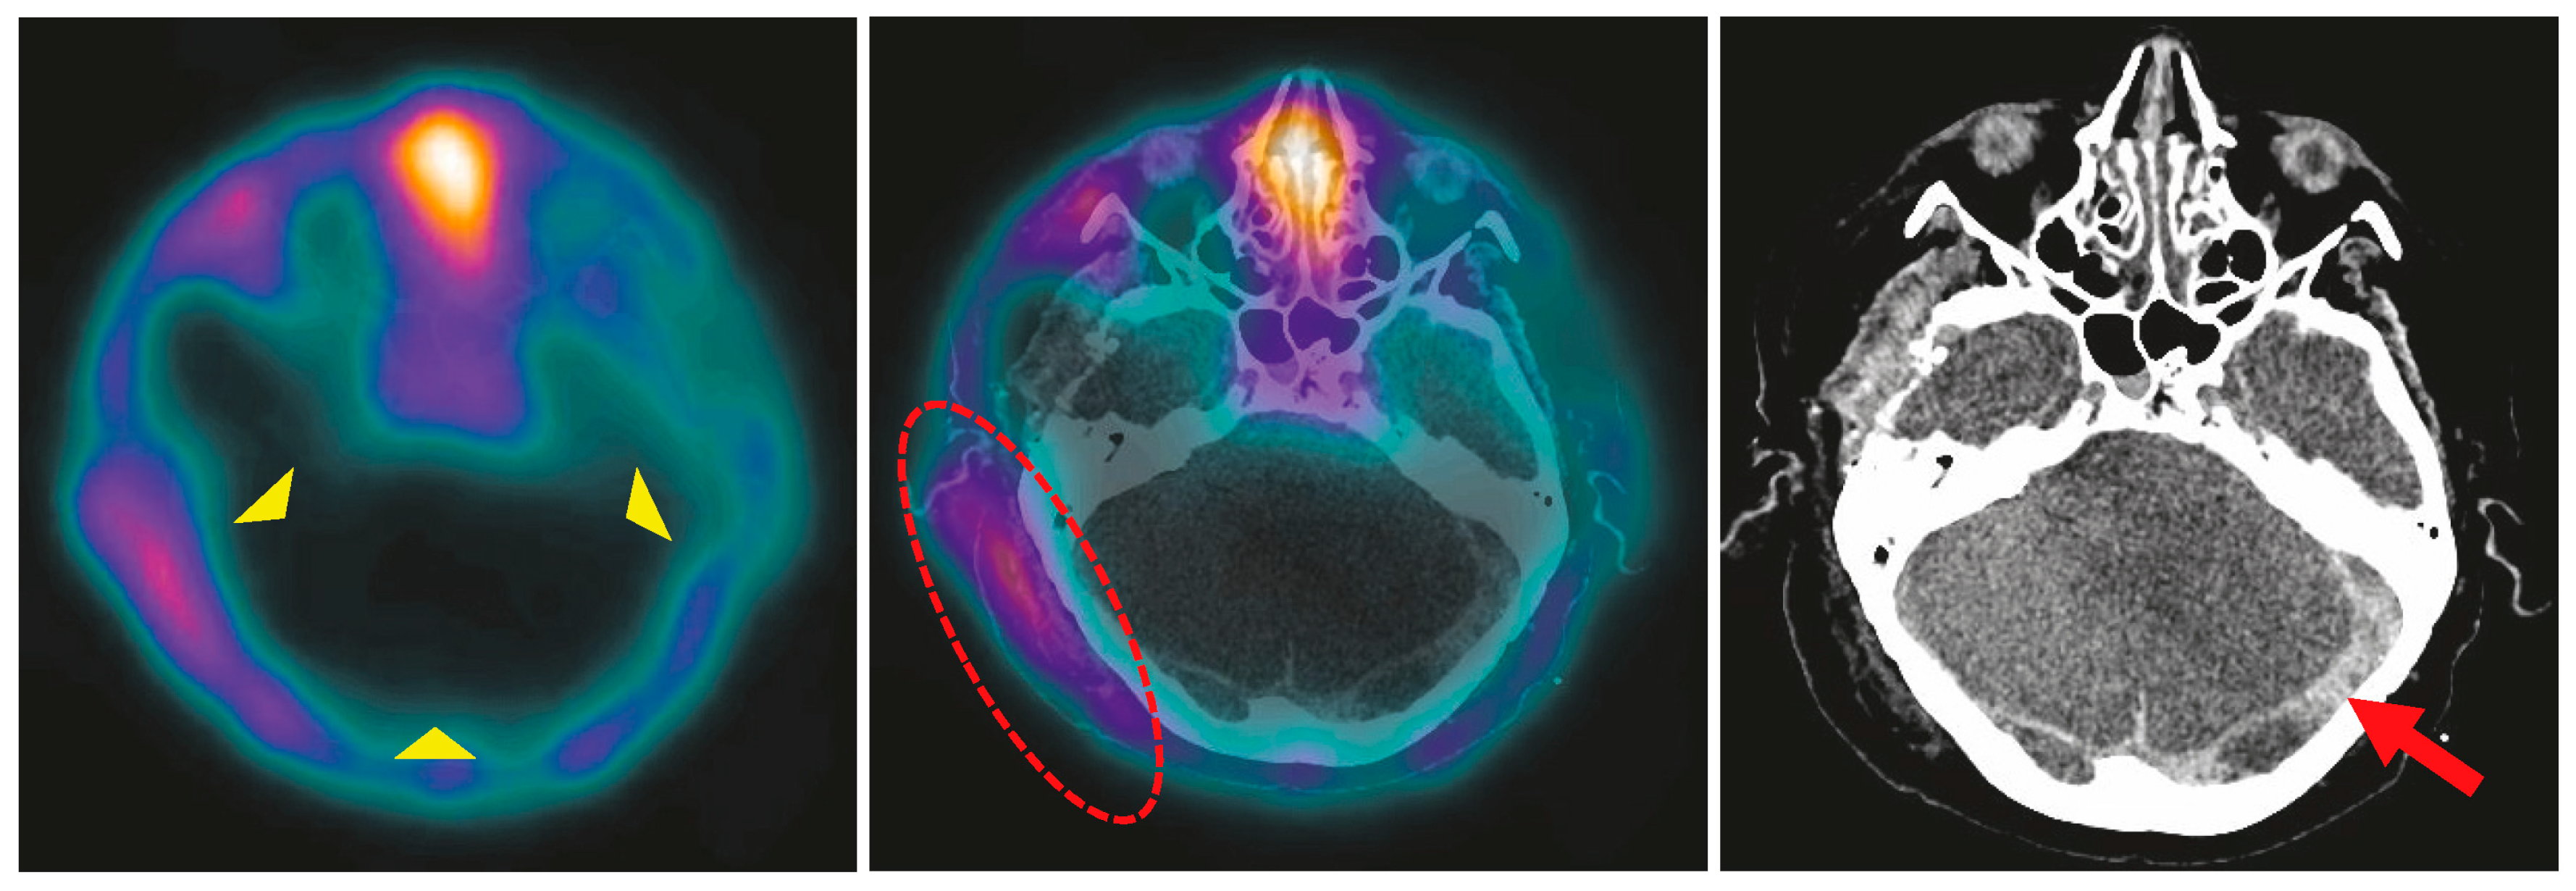

4.3. BPS in Hemicraniectomy